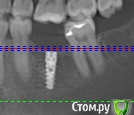

Елена83 Опубликовано 6 февраля, 2016 Автор Поделиться Опубликовано 6 февраля, 2016 вроде симпатичноне переживайте раньше времени сходите на очную консультацию к ортопедуСпасибо!Смутило еще, что с правой стороны(тот же 6 зуб) имплант стоит вполне вертикально без углов. Если можно, посмотрите еще пожалуйста его снимок, темные зоны вокруг импланта означают что он не прижился? Ссылка на комментарий